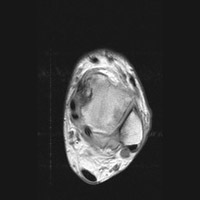

C | Axial MRI. This proton density image of the ankle demonstrates a region of intermediate signal intensity at the lateral aspect, corresponding to edema. |